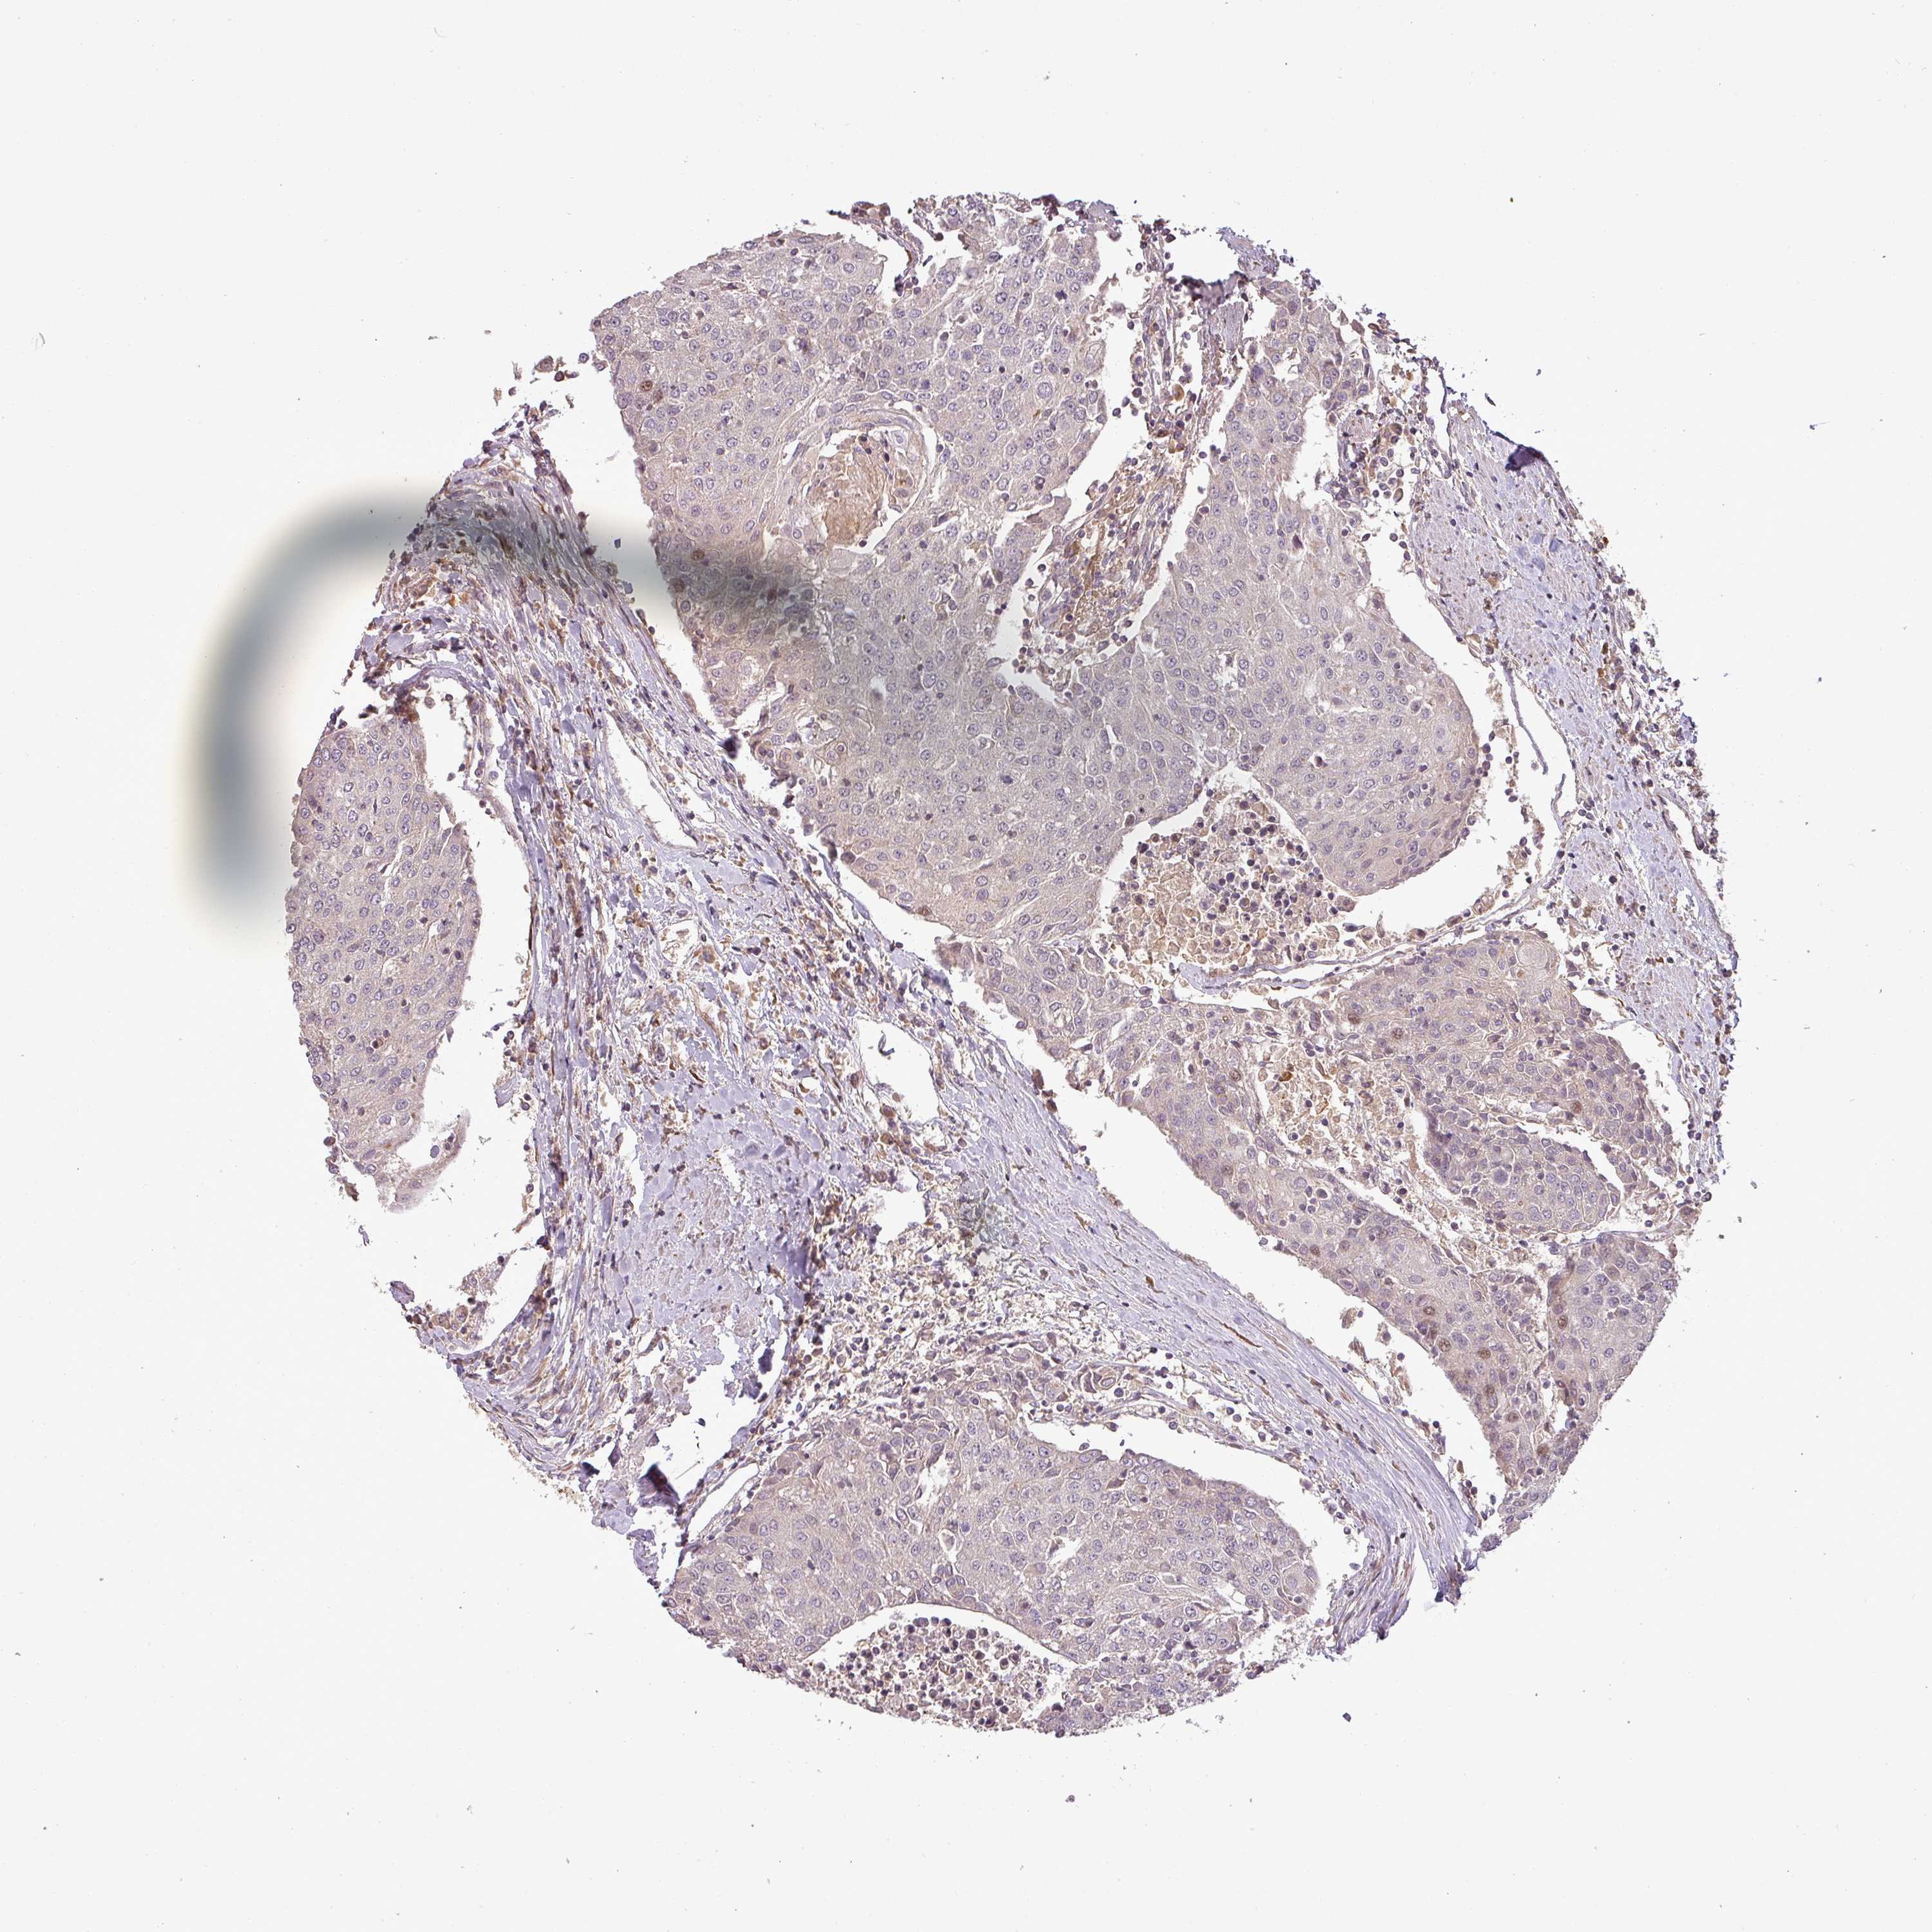

UROTHELIAL CANCER - Protein expressioni

A mouse-over function shows sample information and annotation data. Click on an image to view it in a full screen mode. Samples can be filtered based on level of antibody staining by selecting one or several of the following categories: high, medium, low and not detected. The assay and annotation is described here.

Note that samples used for immunohistochemistry by the Human Protein Atlas do not correspond to samples in the TCGA dataset.

Antibody stainingi

Antibody staining in the annotated cell types in the current human tissue is reported as not detected, low, medium, or high, based on conventional immunohistochemistry profiling in selected tissues. This score is based on the combination of the staining intensity and fraction of stained cells.

Each image is clickable and will lead to virtual microscopy that enables deeper exploration of all samples and also displays staining intensity scores, fraction scores and subcellular localization as well as patient and tissue information for each sample.

Antibody HPA042440

Antibody HPA052209

Urothelial carcinoma, Low grade

Urothelial carcinoma, High grade

Urothelial carcinoma, NOS